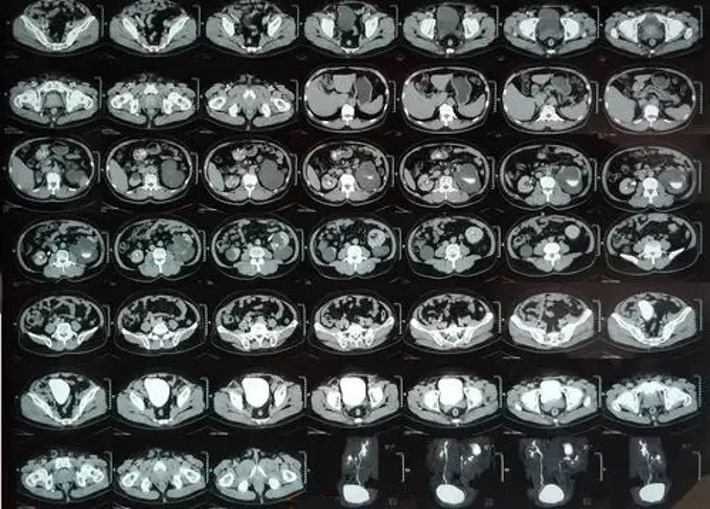

CT es la abreviatura de Computed Tomography en inglés, y su traducción significa tomografía computarizada. El principal medio de inspección utilizado es la radiografía, a través del escaneo penetrante del cuerpo por rayos X, y la imagen de la parte escaneada se obtiene a través de un detector altamente sensible, que tiene las características de escaneo rápido e imagen clara.

El poder de penetración de rayos X es muy fuerte. Al penetrar en el cuerpo humano, formará diferentes tasas de absorción según los diferentes tejidos y las diferentes densidades del cuerpo humano, dejando imágenes en blanco y negro con diferentes escalas de grises en la película fotosensible. Los médicos pueden observar y analizar estas imágenes para conocer el estado de los tejidos internos del cuerpo humano y así hacer un diagnóstico de la enfermedad.

La TC se desarrolla sobre la base de la perspectiva de rayos X. La tomografía computarizada utiliza un dispositivo giratorio para realizar una exploración tomográfica del cuerpo humano, como cortar rodajas de zanahoria. El detector de alta sensibilidad recibe los rayos penetrantes a través del dispositivo giratorio y obtendrá Los datos se ingresan a la computadora y la imagen se reconstruye después de ser decodificada por la computadora.

La estructura principal del equipo de TC tiene tres partes, a saber: la parte de exploración, que se compone de tubos de rayos X, detectores y marcos de exploración; el sistema informático, que almacena y calcula la información y los datos recopilados mediante el escaneo; el sistema de visualización y almacenamiento de imágenes, que Las imágenes procesadas y reconstruidas se muestran en la pantalla del televisor o se toman con varias cámaras o cámaras láser para que las observen los médicos.

El equipo actual de TC se ha actualizado desde la primera generación hasta la quinta generación. Desde el principio, el área de escaneo es pequeña, el tiempo de escaneo es largo (varios segundos), los detectores son pocos (solo uno o dos) y la resolución es muy baja. Hasta ahora, el área de escaneo se ha expandido mucho, la resolución espacial puede alcanzar los 0,4 mm (milímetros), el tiempo de escaneo se reduce a 40 ms (milisegundos) y solo se necesitan 330 ms para escanear 64 capas de imágenes.

El método de escaneo solo se puede traducir desde el principio, y ahora puede realizar escaneo simple, escaneo mejorado y escaneo de contraste, y también puede realizar imágenes dinámicas tridimensionales.

tomografía computarizada

Se pueden ver los detalles de la lesión, la precisión es alta y los resultados del diagnóstico son más seguros. Es la primera opción para el diagnóstico de enfermedades en la cabeza, tórax, corazón, huesos, extremidades, etc.; pero algunos huesos tienen más artefactos, que afectan la visualización de las estructuras de tejido blando circundantes, como la base del cráneo y el canal espinal, etc., y se ven afectados por el movimiento respiratorio, es fácil pasar por alto lesiones pequeñas, como lesiones pequeñas en los pulmones y el hígado.

Además, los rayos X son rayos de alta energía que son dañinos para el cuerpo humano, por lo que las inspecciones frecuentes o prolongadas no son adecuadas. Algunos pacientes con enfermedades graves, como insuficiencia hepática y renal severa, hipertiroidismo, asma y ciertas lesiones alérgicas, no son aptos para este tipo de inspección. .